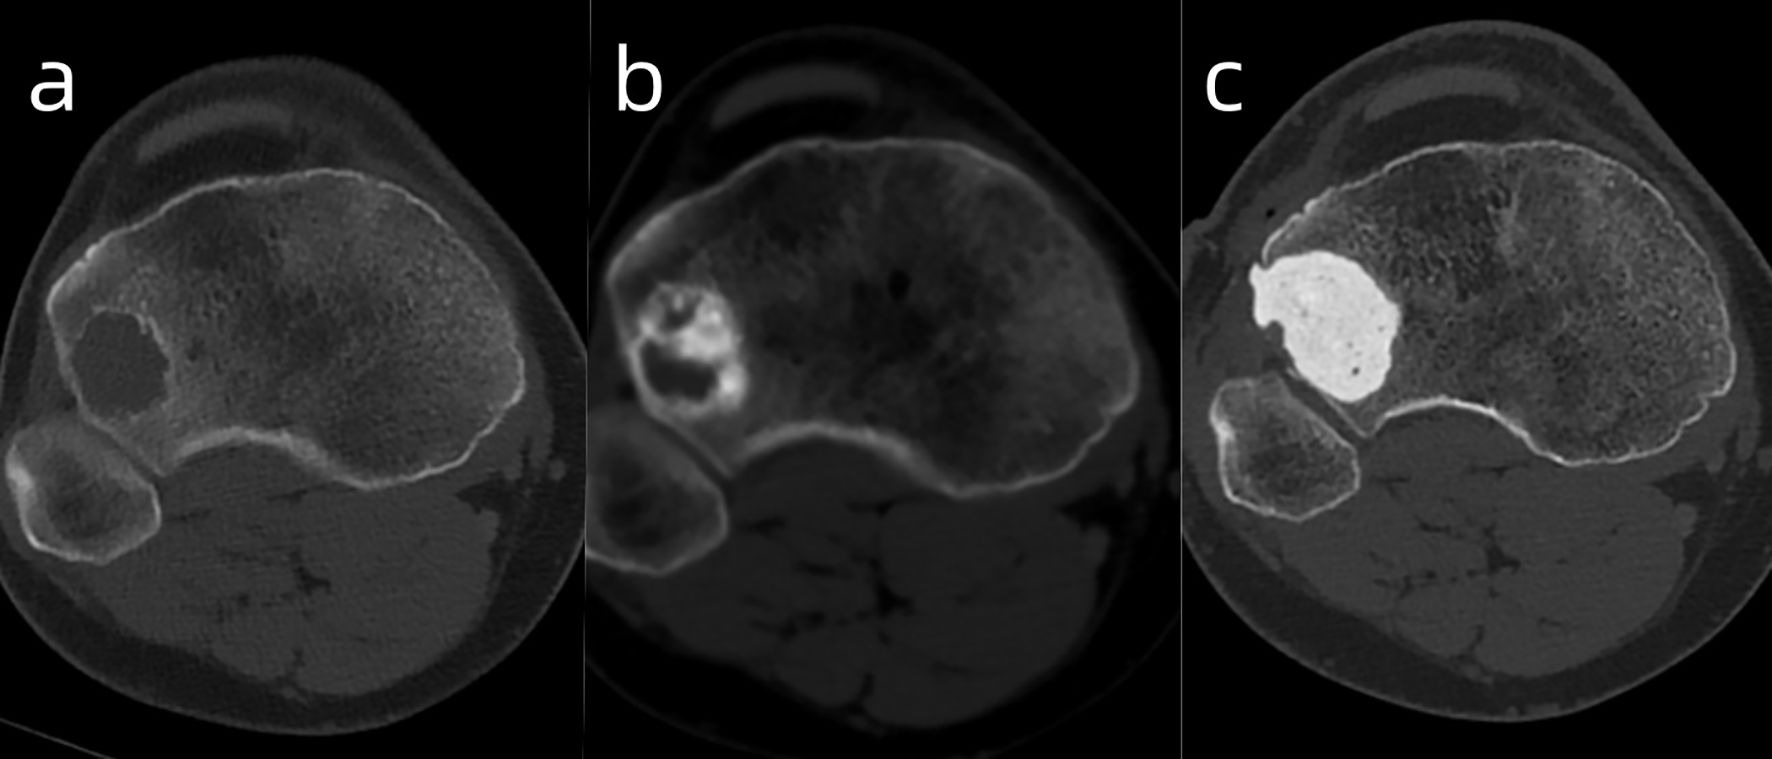

Introduction: Multicentric giant cell tumor of bone is extremely rare, accounting for less than 1% of all giant cell tumor of bone(GCTB) cases. Metachronous multicentric GCTB is even rarer. Case Presentation: We present a rare case of metachronous multicentric giant cell tumor of bone (GCTB) in a 27-year-old male, in whom three distinct lesions developed sequentially over a 10-year period: first in the right distal femur, followed by the proximal femur, and later the proximal tibia. To address progressive disease and prosthetic complications, the patient underwent revision of the mega-prosthesis combined with adjuvant denosumab therapy, followed by curettage of the subsequently emerging tibial lesion. Conclusion: This case illustrates the sequential development of multiple GCTB lesions and the importance of combined surgical reconstruction and denosumab therapy in long-term management.